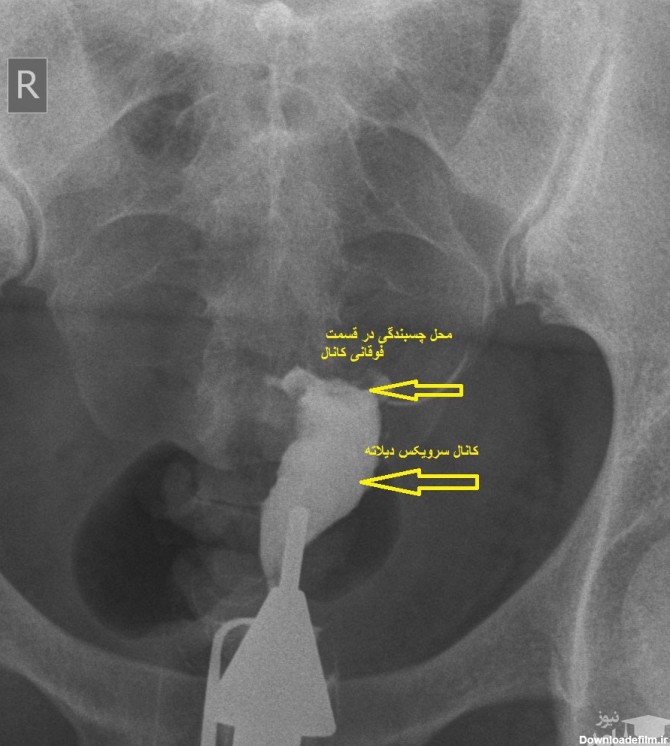

عکس رنگی رحم یا هیستروسالپینگوگرام یک نوع روش رادیولوژی است برای خانم هایی که مشکل باروری دارند انجا

عکس رنگی رحم بدون درد؛ هیستروسالپنگوگرافی برای مشاهده داخل رحم و لوله های فالوپ استفاده می شود. می تواند نشان دهد که داخل رحم اندازه و شکل طبیعی دارد یا خیر.